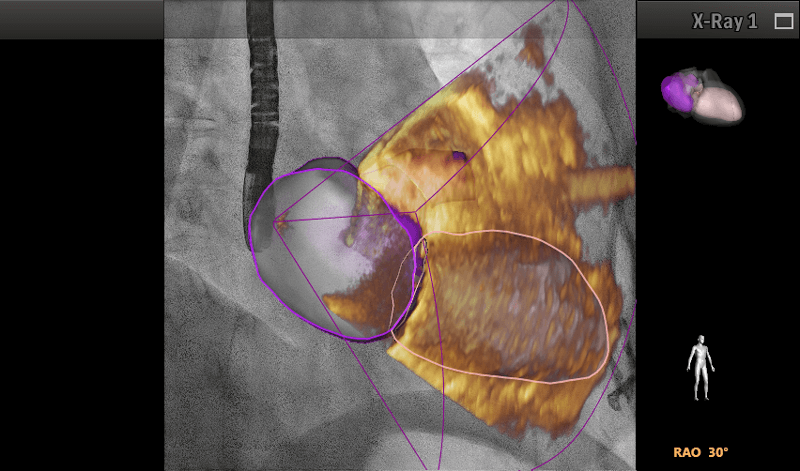

Cardiología estructural: software de fusión con tomografía y resonancia para colocación de TAVI o cierre de orejuela.

Estudios congénitos: fusión de imagen con la sonda transesofágica (Echo Navigator).